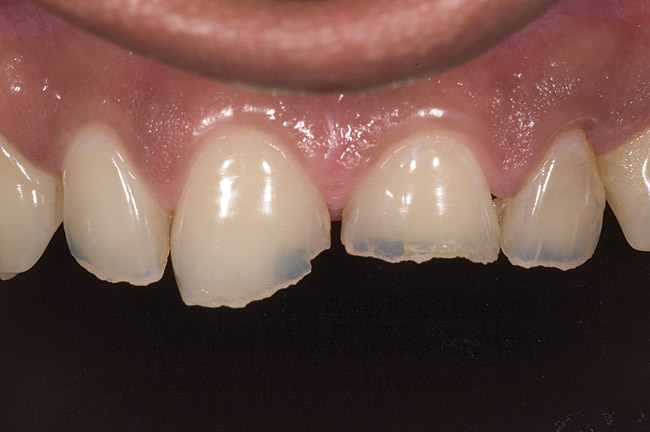

Figure 18  1:1 view of restored palatal surfaces with nanofilled resin.

Figure 18